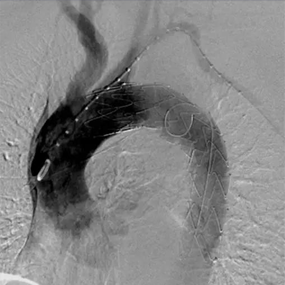

Hercules™ Thoracic Stent Graft System with Low Profile Delivery System is mainly indicated for the treatment of aortic aneurysms confined to straight segments of the blood vessel.